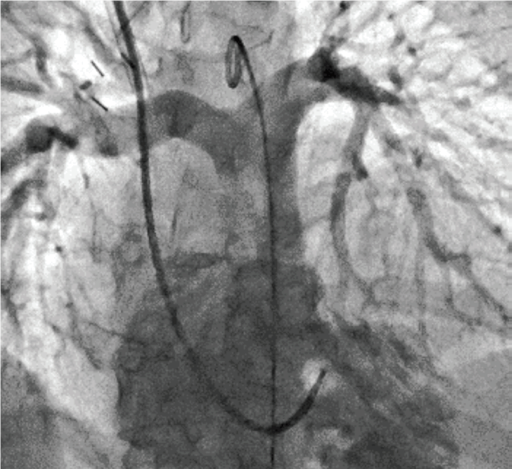

В основу покладена робота в режимі 3D DA або 3D DSA. Зйомку можна виконувати як з операційної, так і з пультової кімнати для зменшення дози на персонал, зі швидкістю обертання С-арки до 50°/с.